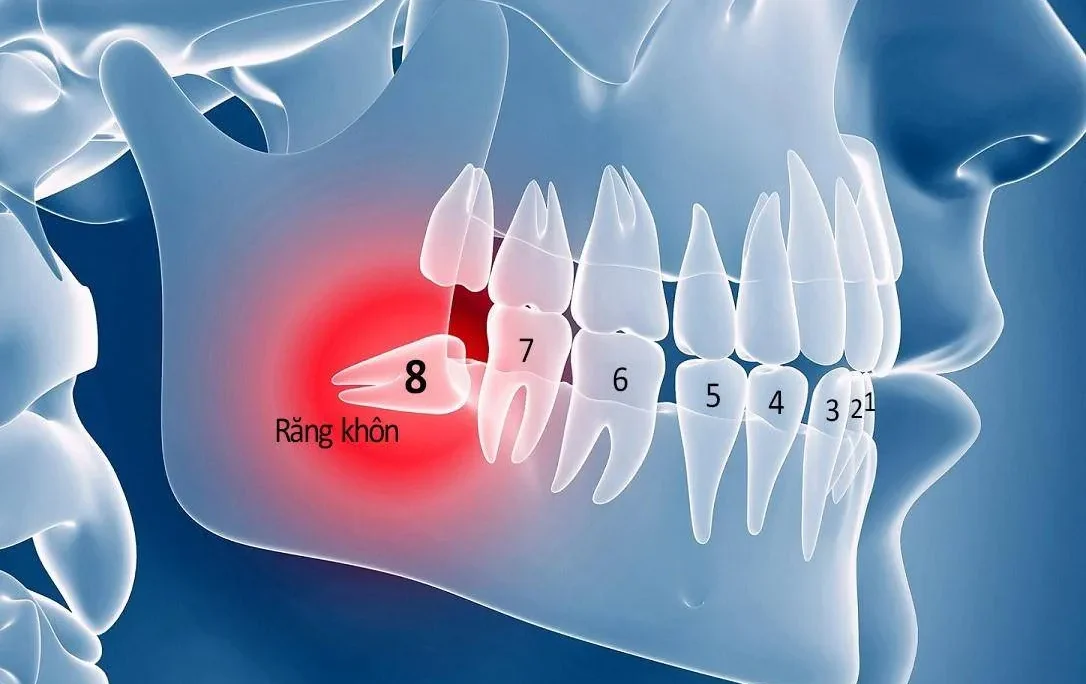

Trong thực tế lấy tủy răng là phương pháp hữu hiệu nhất. Tuy nhiên, theo các chuyên gia nha khoa, phương pháp này chỉ nên áp dụng đối với một số trường hợp. Điều này bởi vì sau khi điều trị thì tủy răng sẽ không còn khỏe được như trước. Bên cạnh đó tuổi thọ của răng cũng có thể bị giảm xuống.

Một số trường hợp nên lấy tủy răng có thể bao gồm:

- Người bị nhiễm trùng tủy hoặc viêm tủy

- Răng có những mảnh vỡ hoặc mẻ lớn

- Sâu răng làm cho tủy răng lộ ra

- Răng đau nhức. Lúc này người bệnh khó chịu khi ăn đồ lạnh hoặc đồ nóng

- Răng có mảnh vỡ hoặc là mẻ lớn

- Thường xuyên bị đau nhức răng, cơn đau lan đến đầu. Thậm chí cơn đau đến tận đêm và không thuyên giảm khi đã uống thuốc. Một thời gian sau, cơn đau có thể hết nhưng tủy đã chết hoặc hoại tử

- Ở lợi gần với chân răng có mụn mủ trắng. Mụn thông thường không đau và chỉ bị một thời gian ngắn rồi biến mất. Tuy nhiên mụn có thể tái phát và có thể dẫn đến nhiễm trùng

- Trường hợp răng mọc lệch hay mọc ngầm nằm sâu trong xương